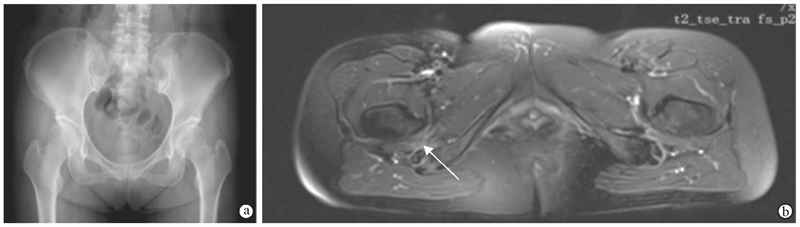

图2 50岁女性患者,骨盆前后位X线片可见髋关节临界性发育不良(a),MRI图像显示股方肌水肿(b,箭头所示)

(图片来自上海交通大学附属第六人民医院骨科病例资料)